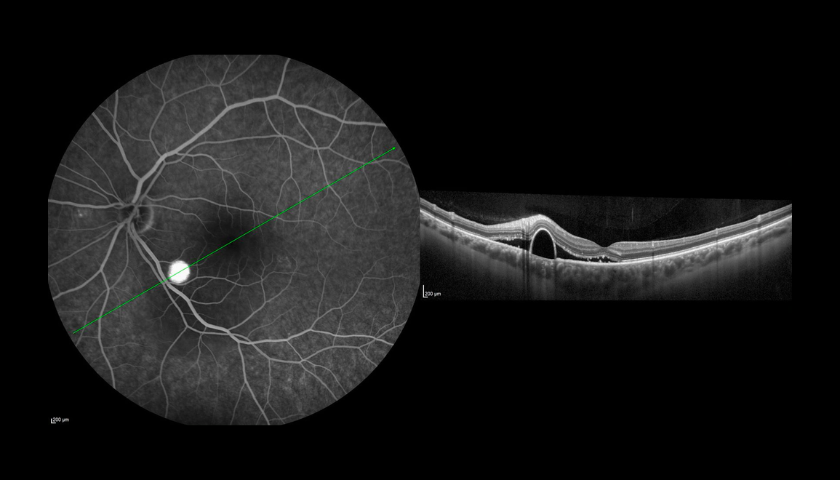

A Angiografia Fluoresceínica (AF) é um exame auxiliar de diagnóstico e monitorização em oftalmologia que permite visualizar e analisar a circulação da retina, com o objetivo de identificar possíveis alterações ou lesões que expliquem um determinado quadro clínico.

A Angiografia é indicada principalmente em patologias como a Retinopatia Diabética (RD), a Degenerescência da Idade (DMI), as oclusões vasculares (tromboses) e os tumores oculares. Utilizando o Spectralis® HRA+OCT (com as lentes de 30o, 55o ou 102o), é um procedimento de diagnóstico no qual uma sequência rápida de fotografias é tirada após injeção de um corante para documentar a circulação sanguínea da Retina e também da Coróide e assim ajudar a diagnosticar e tratar muitas doenças oculares.